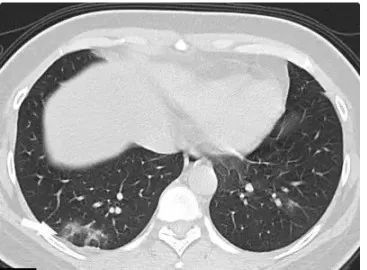

肺炎的CT图片

肺炎的CT图片,正常肺对比肺癌ct图片

肺炎ct图片

普通肺炎ct图片

新冠肺炎ct图片